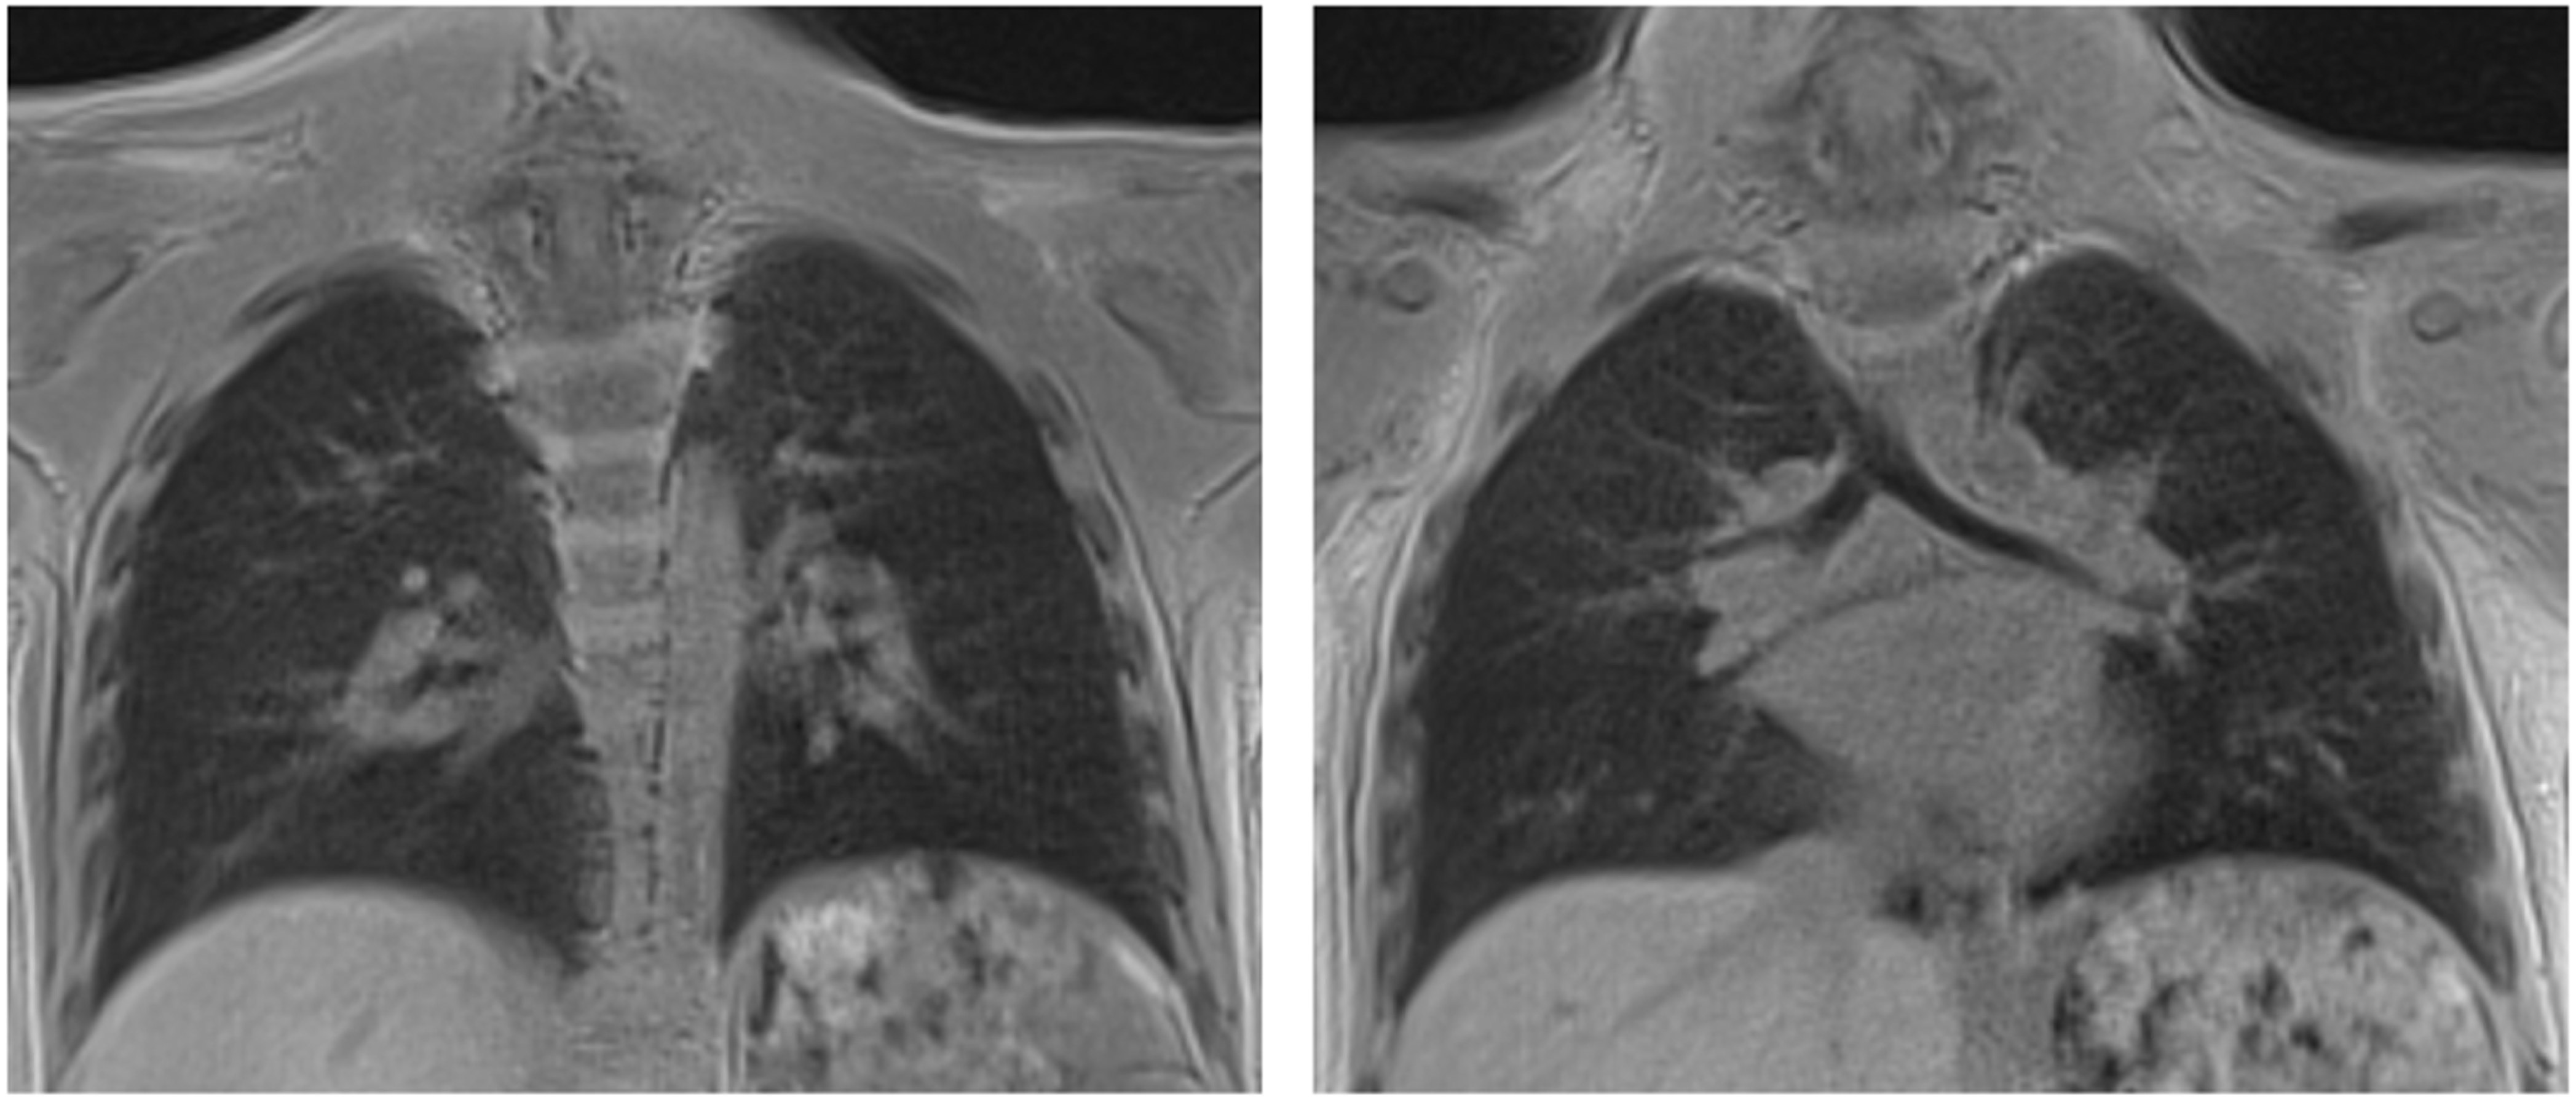

- Tischendorf, P.; Kunnemann, M.D.; Krahling, T.; Lange, J.H.; Heindel, W.; Beck, L. Thoracic MRI in Pediatric Oncology: Feasibility and Image Quality of Post-Contrast Free-Breathing Radial 3D T1 Weighted Imaging. Biomedicines 2025, 13, 2302. [Google Scholar] [CrossRef]